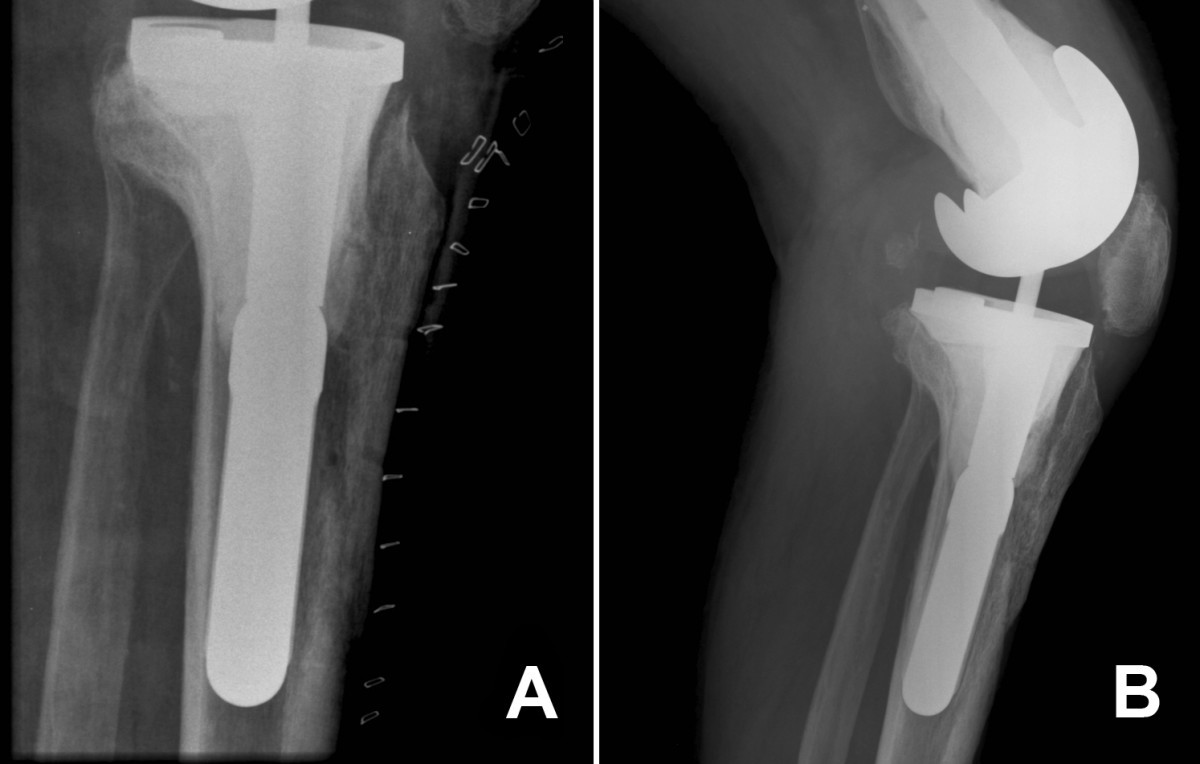

Tibial Tubercle Osteotomy vs the Extensile Medial Parapatellar Approach

Total knee replacement with rotational proximal tibial osteotomy for Tibial Tubercle Osteotomy Knee Brace a tibial tubercle or tuberosity transfer (ttt) is a surgical procedure to realign the tracking of the kneecap (patella). surgical kneecap realignment (also called tibial tubercle osteotomy and elevation) is performed when your kneecap has moved. suggested therapeutic exercise. at the first postoperative visit, the patient’s brace is adjusted, and the hinged knee brace is unlocked. Tibial Tubercle Osteotomy Knee Brace.

From www.arthroplastyjournal.org